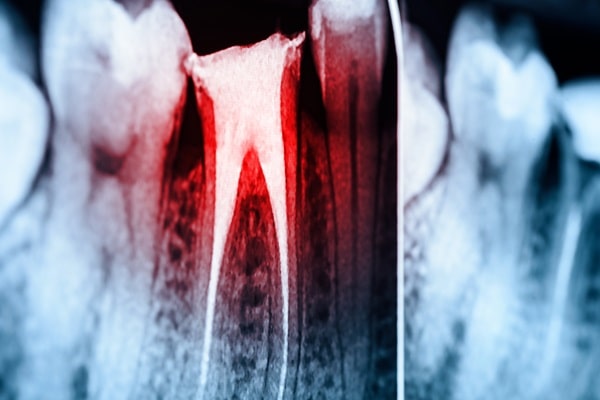

Dental X-Rays

Dental X-rays are commonly used to understand more about your oral health and detect problems that may be present below the gum line. We use digital X-rays in our practice as they provide detailed images for more accurate diagnosis and assist us in developing a more comprehensive treatment plan.

Root Canals

When cavities develop in the enamel (the hard white surface of the tooth), it provides a passage for bacteria to enter the soft dental pulp inside, causing a tooth infection. In such cases, your dentist will treat the tooth with a root canal.